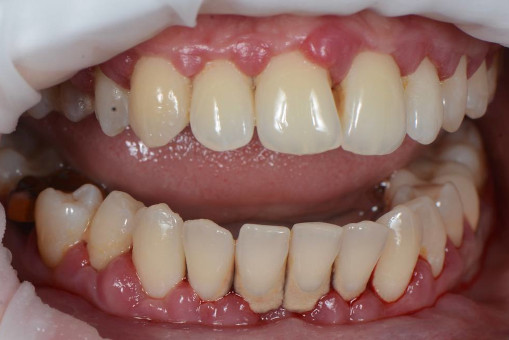

Занимаясь вопросами гигиены уже более 20 лет, мы сформировали четкое сочетание персонифицированной гигиены, нутритивно поддержки и инновационных технологий, имея при этом самое современное,на сегодняшний день, оборудование. Наша технология лечения десен не стоит больших денег и доступна практически каждому! Уникальная комплексная иммуномодулирующая методика лечения десны, в основе которой используется гидротерапия высоким давлением, является нашей гордостью и эксклюзивно внедрена в повседневную стоматологическую практику врачей–пародонтологов сети стоматологических клиник Руссдент.

Философией успеха считаем комплексный подход в лечении, состоящий не только из профессиональных манипуляций врача, но и вовлеченности в процесс пациента, от которого тоже зависит результат стойкой ремиссии. Мы вместе восстанавливаем иммунитет! Иммунитет полости рта. Восстанавливая здоровье десны и «освобождая» пациента от необходимости регулярной профессиональной чистки зубов!

А прежде, чем вы посмотрите фотографии «до» и «после» лечения слизистой оболочки полости рта, проведенных в нашей клинике, хочу поблагодарить большое количество наших пациентов, которые поверили, прониклись нашей концепцией, и мы вместе, именно вместе победили болезни десны, гингивит и пародонтит!

До/после лечения